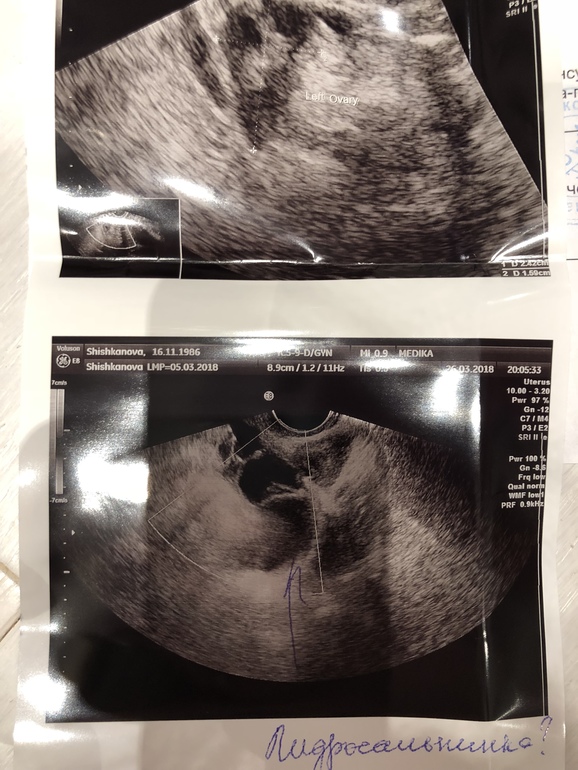

«За маткой, больше справа, рядом с Правым яичником вытянутое образование размерами 52х22 мм с умеренно утолщенными стенками , эхопозитивными перегородками и мелкодисперсной взвесью в структуре содержимого (маточная труба?)»

Предварительный диагноз - гидросальпингс (((((

С перепугу на следующий день (вчера) сходила к ещё одному узисту на другой аппарат - тот же диагноз. (

Вот